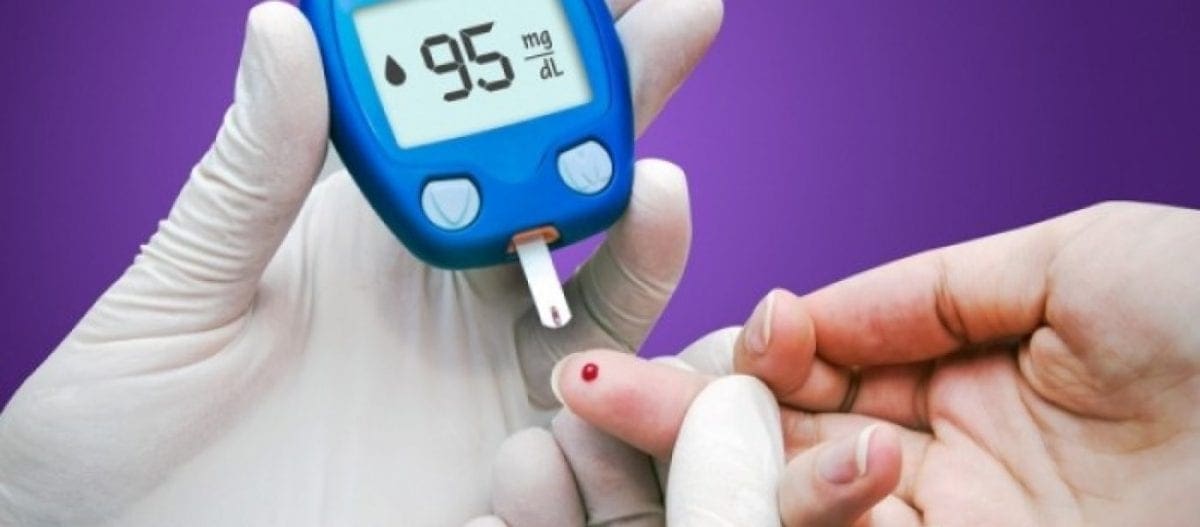

Οι φυσιολογικές τιμές του σακχάρου δεν είναι αυτές ακριβώς που νομίζουμε, αφού ανάμεσα στο υγιές και στο